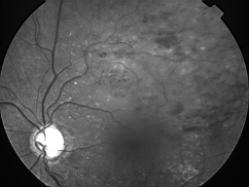

OCCLUSION DE BRANCHE DE LA VTS DE FORME ISCHEMIQUE MAJEURE